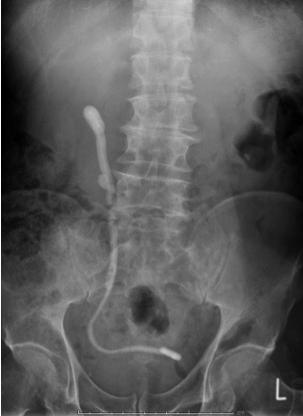

Figure 1

68Ga prostate specific membrane antigen (PSMA) PET/CT: presence of high suspicious area fo prostate cancer (SUVmax 20) in both lobe of the prostate (axial evaluation)

was performed from the skull base to the middle of the thigh Images were processed to obtain PET, CT, and PET CT fusion sections in the axial, coronal, and sagittal planes with a thickness of approximately 0 5 cm by two experienced nuclear medicine specialists, who were blinded to the clinical data The location of focal uptake on 68Ga PSMA PET/TC (Figure 1), three dimensional size, and standardised uptake value (SUVmax) values were reported on a per lesion basis with a sexstant scheme (apex, midgland, and base, each split into left and right) (5) All mpMRI (Prostate Imaging Reporting and Data System “PI RADS” version 2 ≥ 3) and 68GaPSMA PET/CT (SUVmax > 5 g/ml) index lesions underwent targeted cores (mpMRI TPBx and PSMA TPBx: four cores) com bined with extended systematic prostate biopsy (eSPBx: median 18 cores) (2, 14) The procedure was performed transperineally using a tru cut 18 gauge needle (Bard, Covington, GA, USA) under sedation and antibiotic pro phylaxis (17) Prostate targeted cores were obtained using a Hitachi 70 Arietta echograph (Chiba, Japan) supplied by a bi planar trans rectal probe (14) by one urologist with 10 years of experience in cognitive targeted biopsy Data were collected following START criteria (18)